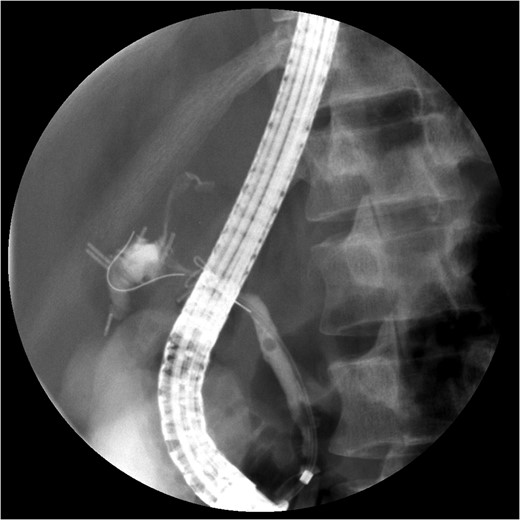

The PTC study confirmed the presence of a completely transected duct, and, fortunately, the ductal injury was traversed with a wire with entry into the distal ductal orifice and into the duodenum (Figs 4–6). Following the procedure, the patient was taken directly to the operating room for open surgical repair.

Percutaneous Transhepatic Cholangiogram with proximal contrast extravasation. Note adjacent surgical clips.